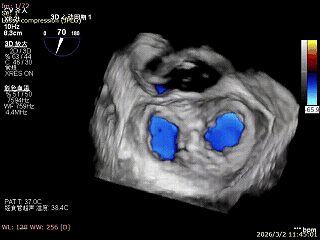

3D enface 切面

3D enface观察反流

双孔组织桥稳定

3D enface反流充分降低